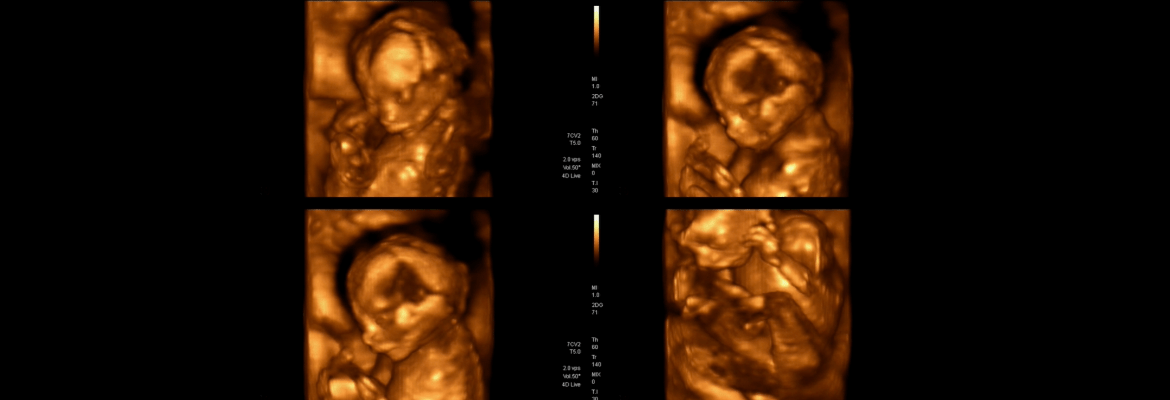

Discover the wonder of your baby’s earliest movements with our 4D ultrasound sessions. Every stretch, yawn, and tiny flutter comes to life in real time, creating an emotional and unforgettable connection for families. Our advanced ultrasound imaging technology delivers crisp, detailed visuals, allowing parents to witness their baby’s development in a vivid, memorable way. With a fetal ultrasound, you gain insight into your baby's growth, offering reassurance throughout your pregnancy.

Each session takes place in a calm and personalized environment designed to make you feel relaxed and valued. Unlike larger clinics, our focus is on giving families time and attention, capturing these special moments without feeling rushed. High-quality images and videos are delivered digitally and in print, allowing you to cherish these memories for years to come. Experience the joy of watching your baby’s first expressions, movements, and milestones with a 4D ultrasound that combines cutting-edge technology and compassionate care.